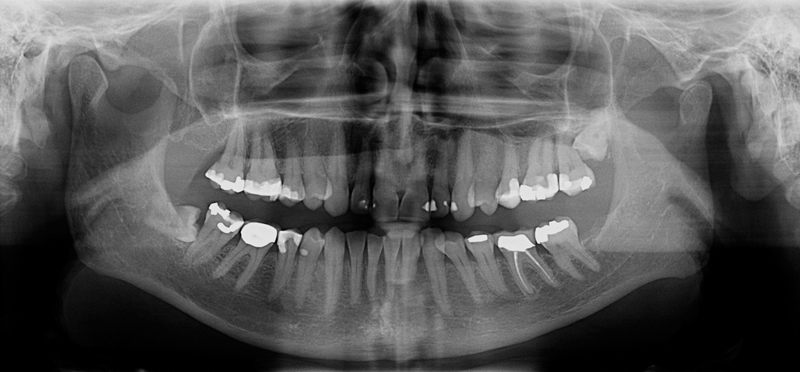

Kjevecyster

Kan være vanskelige å oppdage på annen måte enn ved røntgenbilder.